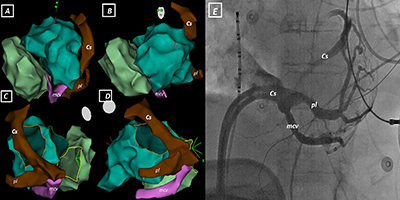

The Last Exit Before the Bridge to Epicardium in Ventricular Tachycardia Ablations: Coronary Venous System

See Videos